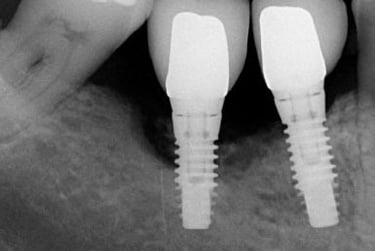

Le temps de cicatrisation d’un implant dentaire varie généralement entre 2 et 6 mois. Cette période permet l’ostéointégration, c’est-à-dire la fusion de l’implant avec l’os. Elle dépend de la qualité osseuse, de l’hygiène bucco-dentaire et du respect des recommandations post-opératoires données par le chirurgien-dentiste.

Implant dentaire durée de vie

La durée de vie d’un implant dentaire est généralement de 15 à 25 ans, voire davantage avec une hygiène rigoureuse et un suivi régulier chez le dentiste. Sa longévité dépend de la qualité osseuse, du mode de vie (tabac, bruxisme) et d’un entretien quotidien adapté pour prévenir toute inflammation péri-implantaire.